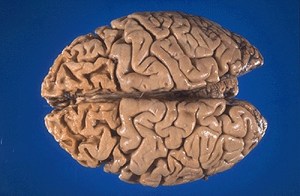

Pick’s disease is a rare disorder that affects the frontal and temporal lobes of the brain, which control speech and personality. These areas of brain undergo slow atrophy. It is therefore classified as a Frontotemporal dementia.

Frontal lobes of brain are responsible for rational emotional responses and the way we act in response to the world around us. In Pick’s Disease it is these frontal lobes that are involved in the disease process. These areas of brain are also responsible for speech and the use of language. As Pick’s disease involves this area of the brain these thinking processes are abnormal in the patients of Pick’s disease.

Brain specimens showing Frontal Lobes thinning in Pick's Disease